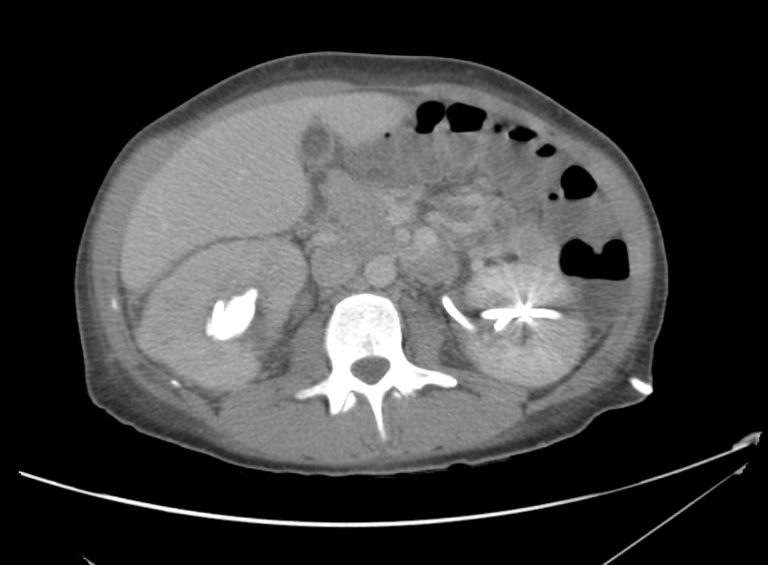

From rabtesting.radiologyacrossborders.org

Loin pain (acute pyelonephritis) Pyelo Nephr Itis Pyelonephritis is generally a complication of an. A kidney infection (pyelonephritis) can be unpleasant, but it will usually improve if treated promptly. acute pyelonephritis is a bacterial infection causing inflammation of the kidneys. acute pyelonephritis is a bacterial infection of the kidney and renal pelvis and should be suspected in patients with flank pain and laboratory. If not. Pyelo Nephr Itis.